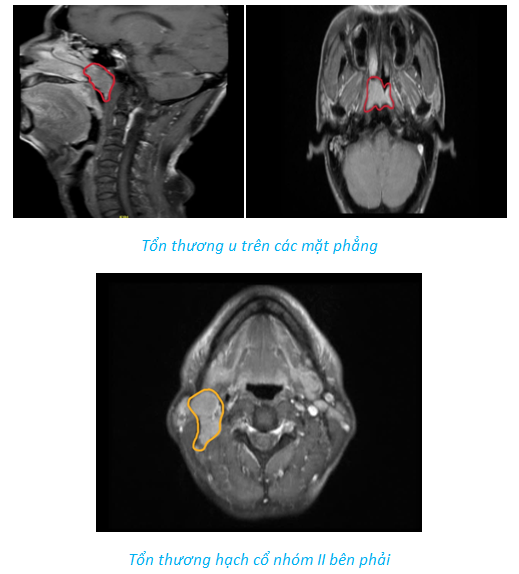

Bệnh nhân 62 tuổi được chẩn đoán ung thư vòm họng cT3N2M0 vào tháng 4/2024. Các tổn thương bao gồm:

- Tổn thương u trên các mặt phẳng.

- Tổn thương hạch cổ nhóm II bên phải.

Sau khi thực hiện hóa xạ đồng thời, vào thời điểm tháng 6/2024, tổn thương đã không còn thấy trên phim cộng hưởng từ.